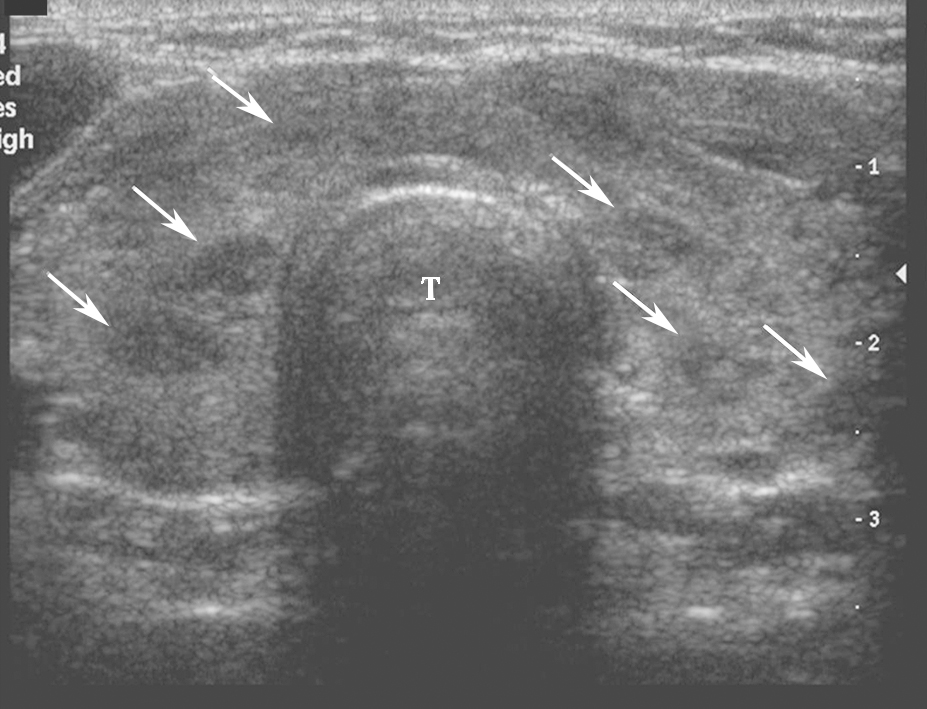

(十一)甲状腺髓样癌

甲状腺髓样癌超声上多为不规则低回声实性结节,内部回声不均,部分病例可伴有囊性成分,髓样癌丰富的血流信号是其超声主要特点。约1/3的髓样癌超声表现不典型,除了血供丰富表现外,类似良性结节(图13、图14)。

,分叶状,可见囊性成分及点状强回声(微小钙化).jpg)

图13左侧颈部纵切面:甲状腺左叶中部中低回声(箭头所示),分叶状,可见囊性成分及点状强回声(微小钙化)

:甲状腺左叶中部中低回声内部彩色多普勒血流信号丰富而杂乱.jpg)

图14左侧颈部纵切面(与图3-3-13同患者、同切面):甲状腺左叶中部中低回声内部彩色多普勒血流信号丰富而杂乱